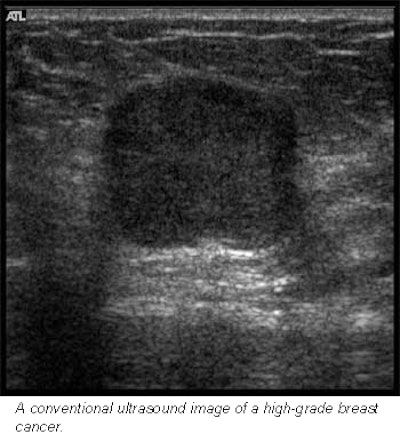

Hoping to ascertain the clinical worth of this new technology, Barr evaluated 100 breast lesions with both conventional and compound imaging. All 200 images were then read both randomly and side-by-side, in which both images of the same lesion were compared.

In the random analysis, viewers rated 91% of the compound images excellent in terms of margin definition, as well as near-field, lesion, and anatomic details. In the comparative analysis, compound ultrasound rated similar to conventional ultrasound in 82% of patients in depicting near-field detail and small structures such as ducts. And it rated better than conventional ultrasound in all patients for margin and lesion definition, as well as reduced speckle.

![]() |

This last advantage -- less noise and clutter -- allows radiologists to examine minute structures like never before, Barr said. With conventional ultrasound, more patients had to be re-scanned or aspirated to determine if a mass was a tumor.

"Now, we can see if a tumor has advanced into a duct," Barr said. "Sometimes, these things are very small, and only with compound imaging can you tell if something is clutter noise or if it’s real."

Barr did find, however, that compound imaging lagged behind conventional ultrasound in shadowing and through-transmission. As he explained, shadowing occurs when sound waves hit a dense mass, such as a calcification. In these cases, the sound waves don’t penetrate and instead bounce back, leaving a black, shadowy area on the scan. This mark appears crisp on a conventional scan, but is unfortunately diluted in a compound image, he said.